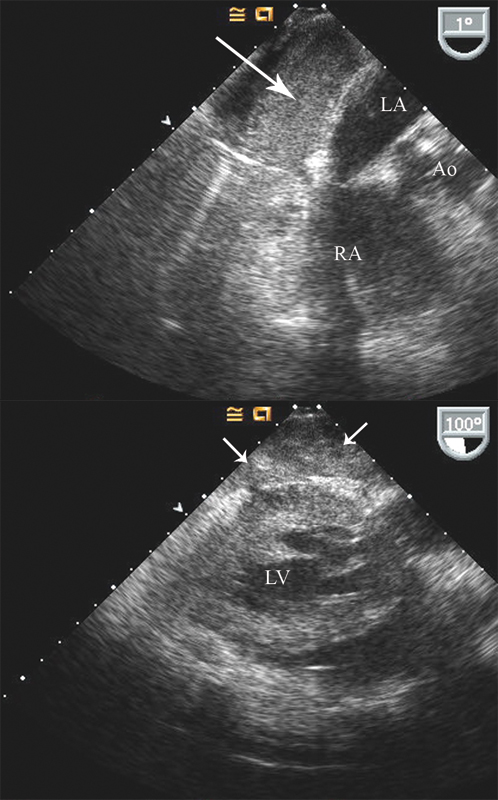

فحوصات تشخيصية لبعض امراض القلب والشرايين التاجية